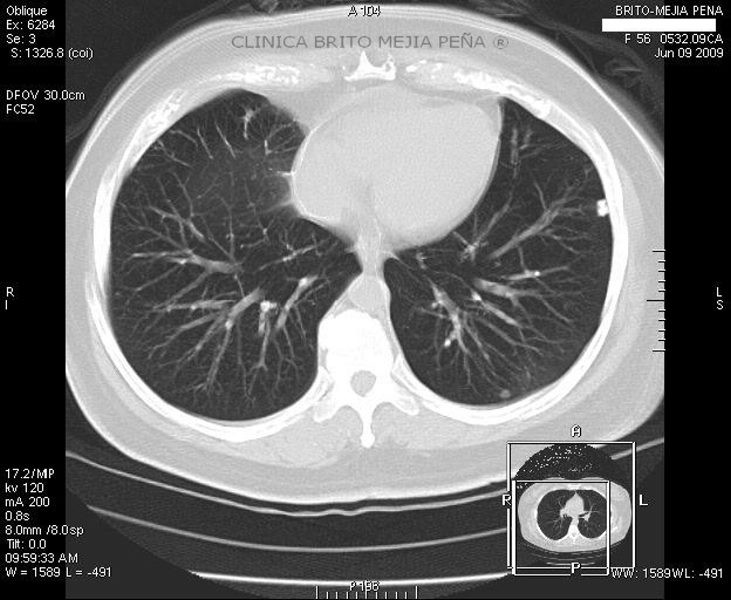

Trombosis arteria pulmonar axial

Post Image